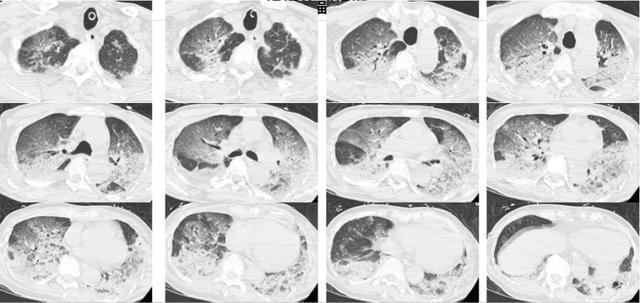

入院时,韩爷爷意识不清,血压、心率下降,医生随即为他安排头颅、胸部CT和肺血管CTA检查,结果显示,老人的双肺出现大面积白色影像。经会诊,韩爷爷被确诊为热射病诱发的肺水肿。

图源:潮新闻